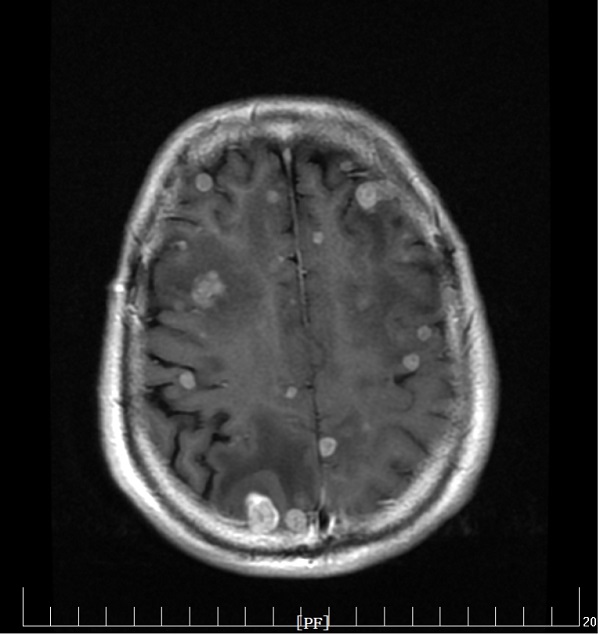

充分研究病情后,刘娟妮主任团队积极与家属沟通,对症治疗的同时,在CT引导下行经皮肺穿刺活检术,术后病理提示:中分化腺癌,基因检测结果提示:EGFR Exon19突变。明确诊断后,刘娟妮主任团队一边安慰患者及家属的情绪,一边对患者的全身状况及疾病进行了充分的评估,邀请相关科室会诊,经MDT讨论并结合患者目前症状、基因检测结果分析及国内外最新指南推荐,制定了个性化的治疗方案,给予口服三代靶向药控制肿瘤。治疗1个月后,复查头颅MRI及胸部CT,结果显示患者肺原发肿瘤、脑多发转移瘤较前均缩小、部分消失。

治疗前

治疗后